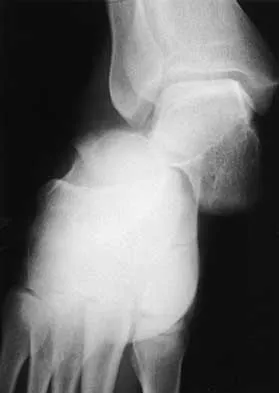

The condition shown in Figures 9a and 9b is most likely the result of

Explanation

The clinical photograph and radiograph show gout, which is the result of urate deposition in the joint and soft tissues. Radiographs frequently reveal periarticular erosions. The crystals are intracellular and negatively birefringent under the polarized microscope. Treatment for acute flares include colchicines, indomethacin, and corticosteroids (including injections). Medications such as allopurinol help prevent recurrent flares. Tophi such as that seen in this patient are often confused with and associated with infection. Wortmann RL, Kelley WM: Crystal-induced inflammation: Gout and hyperuricemia, in Harris ED, Budd RC, Firestein GS, et al (eds): Kelley's Textbook of Rheumatology, ed 7. New York, NY, Elsevier Science, 2005, pp 1402-1429. Trumble TE (ed): Hand Surgery Update 3: Hand, Elbow, & Shoulder. Rosemont, IL, American Society for Surgery of the Hand, 2003, pp 433-457.